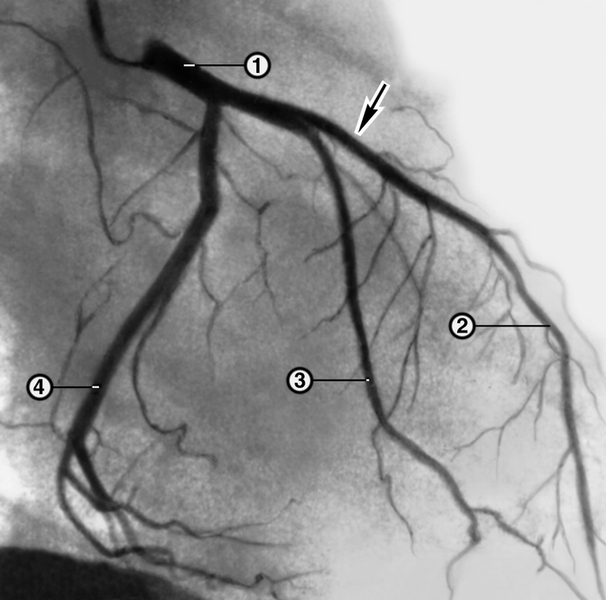

Анатомия коронарных артерий: КТ-изображения